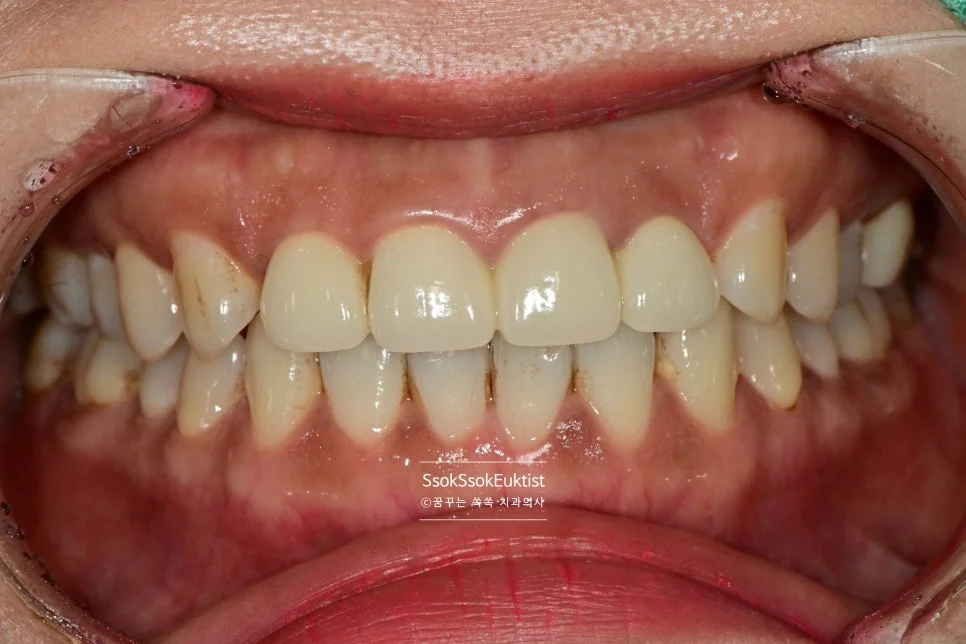

스케일링 전 구강 정면 임상 사진

구강 정면 — 관리가 조금 필요해 보이지만…

이 증례에서도 사진을 보면 구강 내 관리가 조금 필요해 보입니다만,

스케일링 전 치석 착색 상태

Before — 스케일링 전

수면 스케일링 후 깨끗한 치아

After — 수면 스케일링 후

왼쪽 위 치경부 우식을 레진으로 예쁘게 치료한 후 스케일링도 시행하였는데요. 비교적 깨끗하고 건강해진 모습이 보입니다~^^